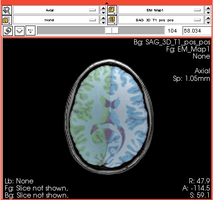

Comprehensive Longitudinal Investigation of Multiple Sclerosis at Brigham and Women’s Hospital (CLIMB) Study

- Collaborator: Svetlana Egorova MD/PhD (Brigham and Women's Hospital(BWH)), Alexander Zaitsev PhD (BWH)

- Short description: Provide Basic EM Segmentation for estimation of brain parenchymal fraction (BPF) . The processing is being performed for the cases with failing PD TDS+ segmentation. The T1-type scans are segmented and registered to PD/T2 images. The requests are being submitted over the Web GUI.

- Image specification: 1.5 Tesla ,Scanner: Varies among participants.

- Used Task: MRI Human Brain Hemisphere